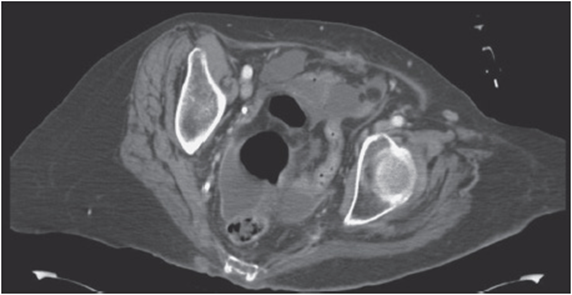

Six days later, while on call for the general surgery service, you are asked to evaluate the same patient who has been recovering uneventfully until now. He complains of new mild pelvic discomfort, anorexia, and difficulty voiding. His bowel function has not yet returned. He has a low-grade fever, mild tachycardia, and moderate right lower quadrant tenderness to deep palpation. A CBC with differential reveals leukocytosis with neutrophil predominance. CT of his abdomen and pelvis with oral and intravenous contrast reveals a 6-cm rim-enhancing pelvic fluid collection surrounding the rectal stump (see Figure 22-1).

Figure 22-1. Axial CT of a postoperative pelvic fluid collection.